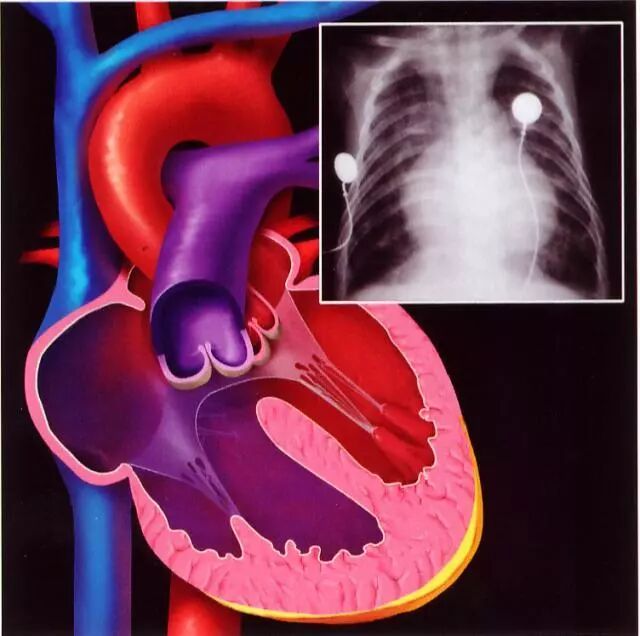

先天性心脏病的症状表现视乎先天性心脏病的类型和病情复杂程度而言。先天性心脏病根可分为这几类:

无分流类:左右两侧无分流、无紫绀,如肺动脉口狭窄、主动脉狭窄、主动脉缩窄、原发性肺动脉扩张、原发性肺动脉高压或右位心等。

左至右分流类:在左右心腔或主肺动脉间有异常通道,左侧压力高于右侧,左侧动脉血通过异常通道进入右侧静脉血中。

右至左分流类:右心腔或肺动脉内压力异常增高,血流通过异常通道流入左心腔或主动脉。